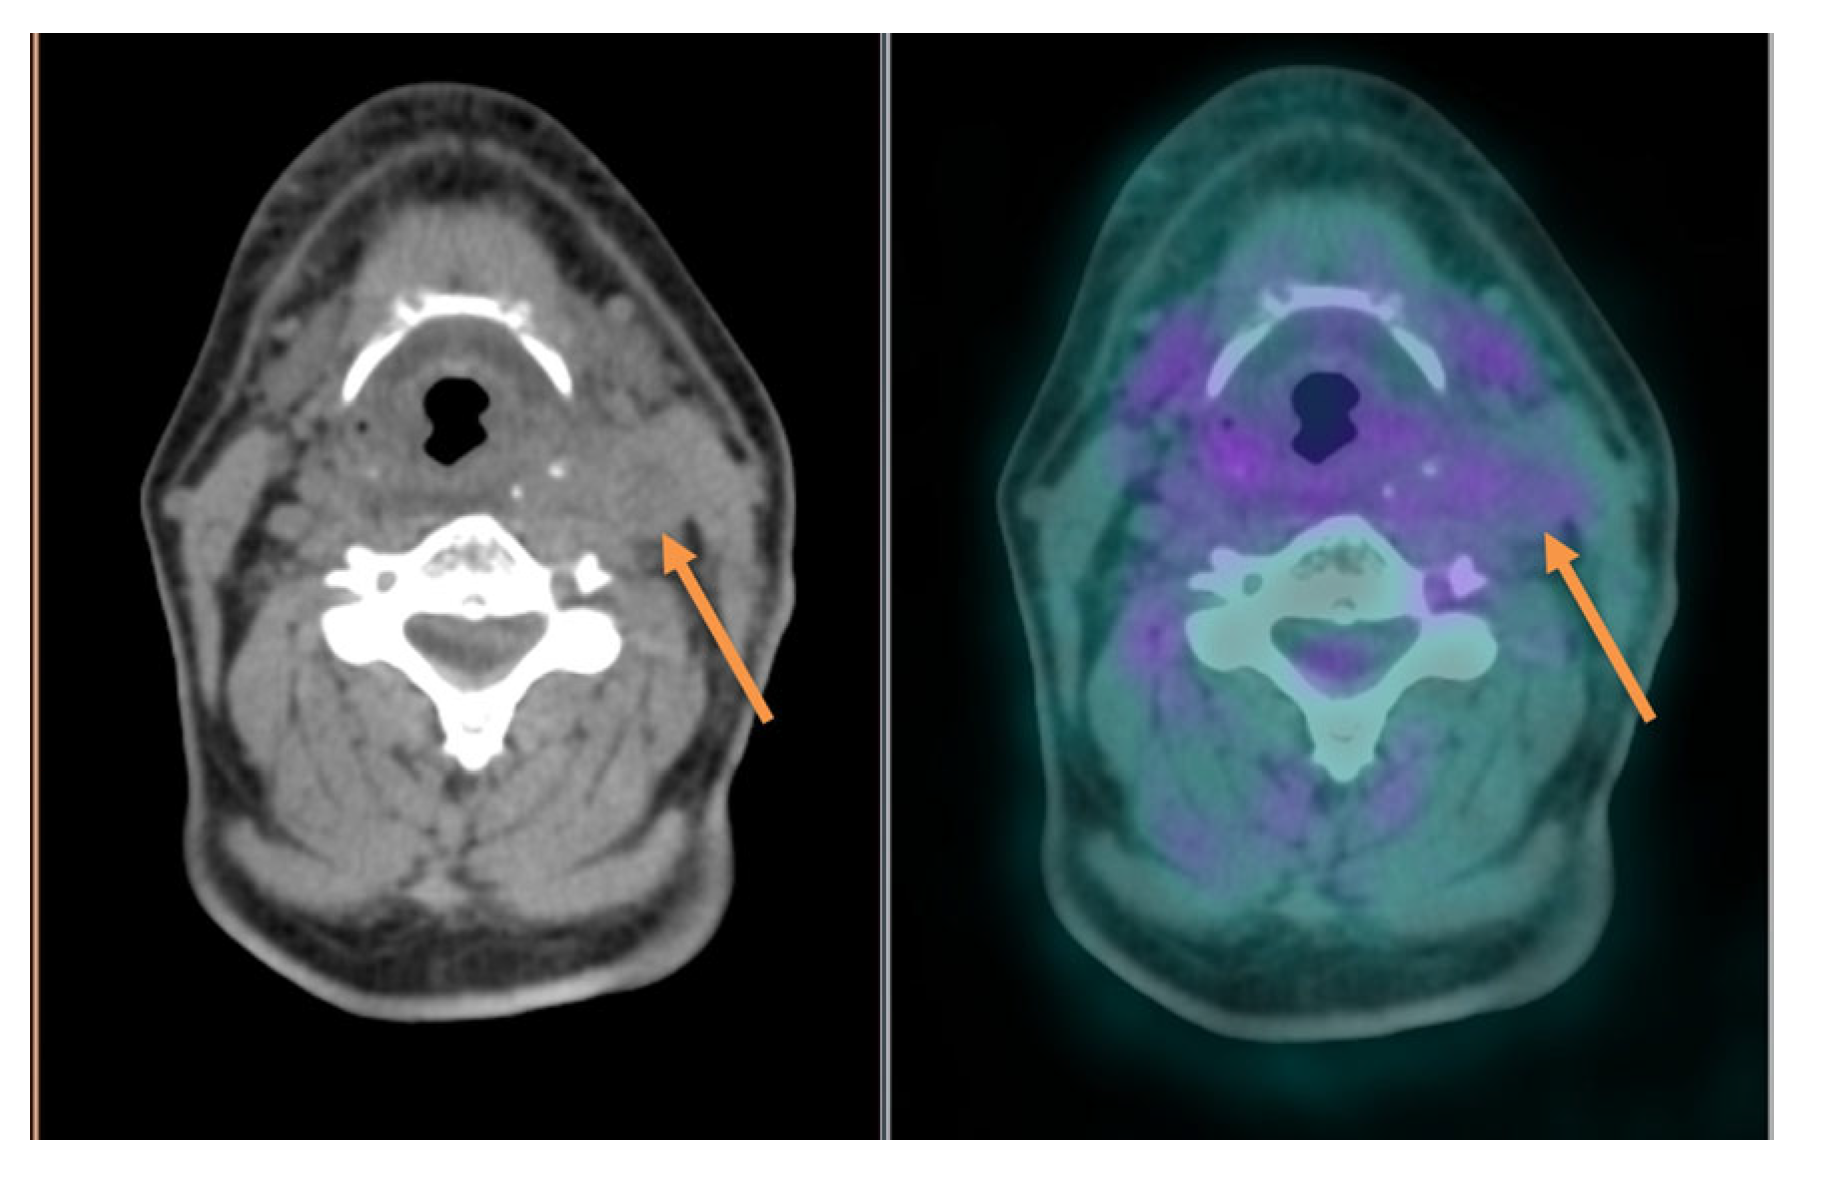

| Selection and delineation of GTV | - Detection of occult primary tumor (see text) - Tumor extension not defined on CT or MRI (see Figure 3) |